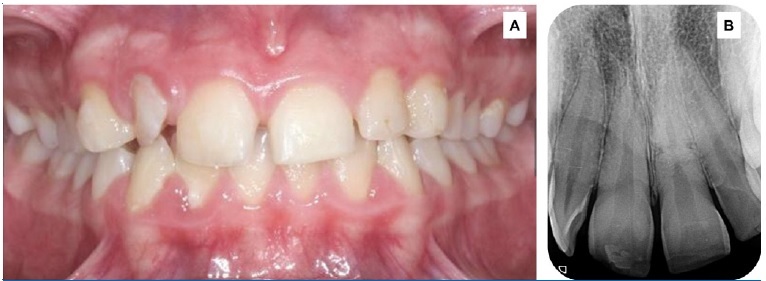

A 14-year-old female patient with good general health attended the dental office immediately after an accident during physical education class. The clinical examination showed incisal unevenness, local bleeding, increased mobility, and displacement of the permanent maxillary left central incisor tooth from its alveolus (Figure 1A). The radiographic assessment demonstrated increased periodontal ligament space and a transverse line in the middle third of the root with coronal fragment extrusion (Figure 1B).